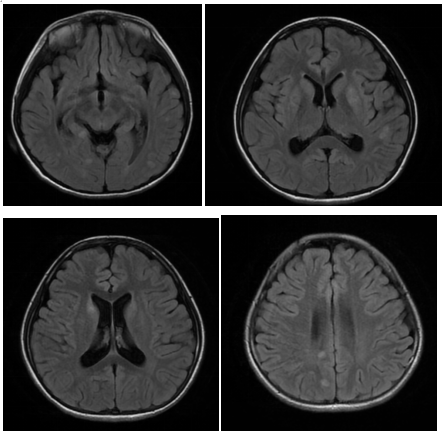

碩碩起病急、進展迅速,若不及時治療很可能發(fā)展為重癥并危及到生命。入院后醫(yī)生馬上展開救治。進行詳細查體和追問病史,及時完善抽血化驗、腰椎穿刺、頭顱+全脊髓核磁共振等系列檢查,最終,迷霧散去、真相浮出水面——碩碩患的就是急性播散性腦脊髓炎。

核磁共振影像